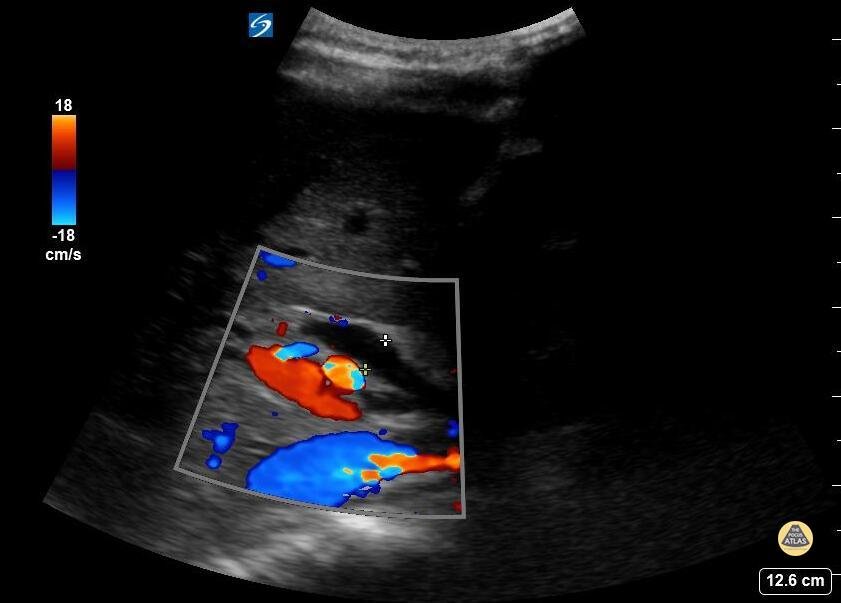

11 year old female with abd pain and emesis. Kicked in stomach by horse 6 weeks prior with grade 4 liver lac. Seen a few days ago with reassuring labs and US. Now with rising aminases and bilirubin. POCUS demonstrated a dilated and edematous gallbladder with sludge, and a dilated CBD and the classic 'double barrel' sign. Contributed by: Matthew Moake, MD PhD